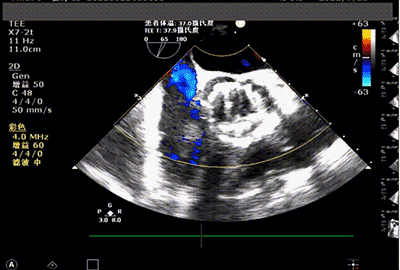

术后即刻食道超声

食道彩超

心超提示:瓣膜位置形态良好,无瓣周漏,手术效果非常好。